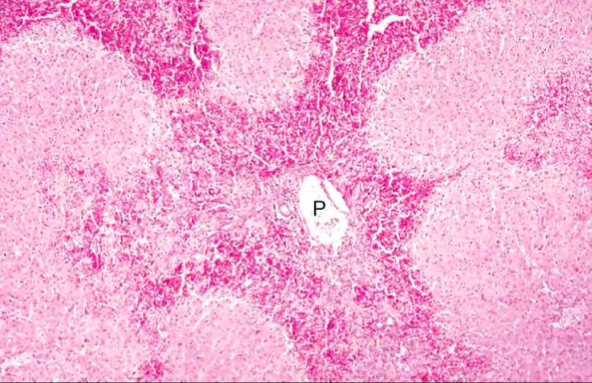

Zone 1, Periportal necrosis. Horse liver P = portal area. Etiology is often toxic